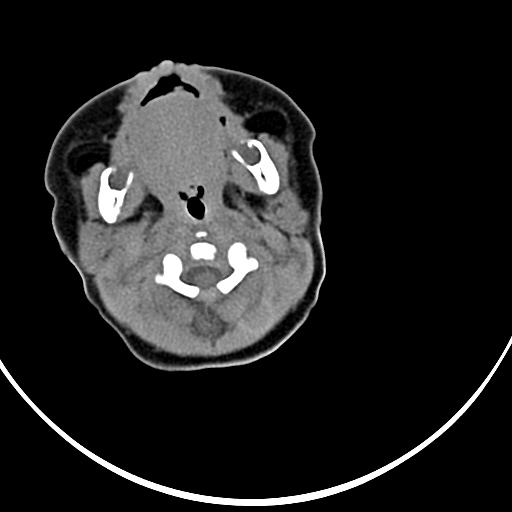

患者,男,1月,出生后一月,无明显诱因出现颈部左前方肿块。体检:左侧颈部轻度凸起包块,触之较硬。

患者,男,1月,左经部轻度凸起包块,质硬。

病灶与左侧胸锁乳突肌分界不清,软组织密度,不似囊性改变,从病人的年龄及病变性状首先要除外先天性斜颈(肌性斜颈)可能。

左侧胸锁乳突肌肿大,考虑产伤所致

胸锁乳突肌挛缩(斜颈)?